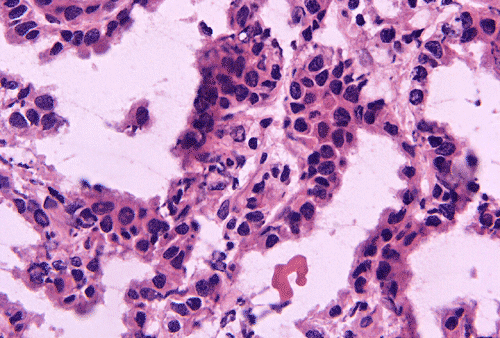

Intraoperative cytologic preparation (Panel C) shows clumps of cells that do not smear out. In between these large clumps are scattered single cells that contain a moderate amount of cytoplasm. On high magnification (Panel D), a papillary pattern is demonstrated in some of the cellular clumps. The nuclei are round to oval, rather monotonous and bland. These cells contain a moderate amount of amphophilic cytoplasm and a well-defined cell membrane.

Permanent sections show a papillary epithelial neoplasm with invasion into the brain parenchyma (Panel G, H, and I ). In all areas the tumor cells maintained a single layered architecture. While a papillary structure is present in some area, the tumor cells arrange in a back-to-back cystic architecture intervened by a thin layer of fibrovascular stroma (Panel J). The nuclei are rather bland and monotonous. Mitotic figures are not readily seen  (Panel K). On immunohistochemistry, practically all tumor cells strongly express S100 protein (Panel L) and vimentin (Panel M). Most tumor cells are positive for cytokeratin (AE1/AE3) (Panel N). GFAP is expressed by some tumor cells (Panel O). The Ki-67 labeling index is about 1-2% (Panel P).